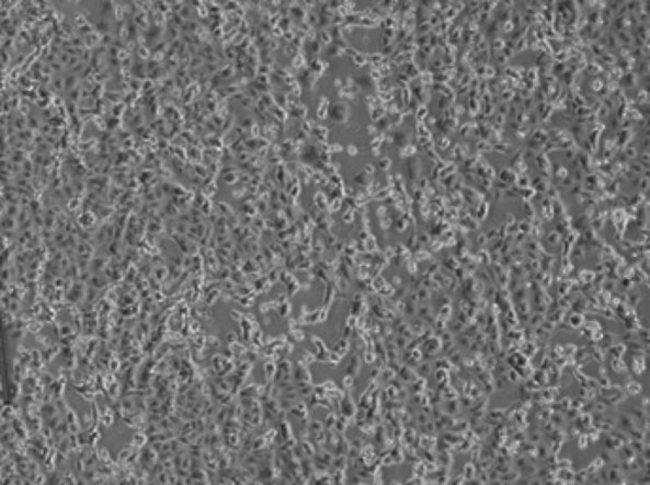

L’eccellente risultato è stato ottenuto dai virologi a meno di 48 ore dalla diagnosi di positività per questi due pazienti. “È un passo fondamentale” spiegano i ricercatori “che permetterà di perfezionare i metodi diagnostici esistenti e allestirne di nuovi”.

“La sequenza parziale del virus isolato nei laboratori dello Spallanzani, denominato 2019-nCoV/Italy-INMI1, è già stata depositata nel database GenBank ed a breve anche il virus sarà reso disponibile per la comunità scientifica internazionale”, ha commentato Marta Branca, direttore generale dell’istituto.